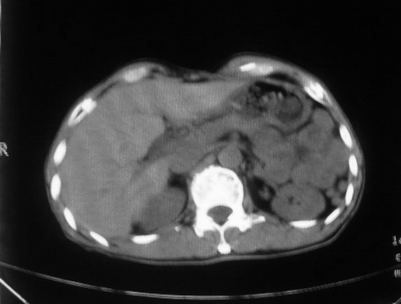

男,66岁,贲门ca术后一年,喝了5、6杯水了。怎么描述跟诊断啊